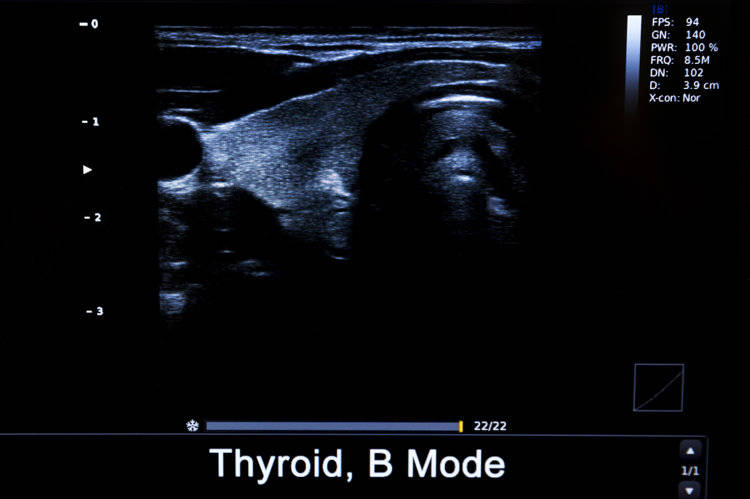

最后是甲状腺结节。它是甲状腺组织内出现的局限性肿块,最大的特点是会随着吞咽动作上下移动。中国医学科学院肿瘤医院山西医院头颈外科主任李德志介绍,在B超检查中,20~30%的人会检出大小不一的甲状腺结节,其中绝大部分为良性,最终被诊断为恶性的概率仅有3~4%。即便如此,普通人也建议每年进行一次甲状腺检查,避免遗漏恶性风险。